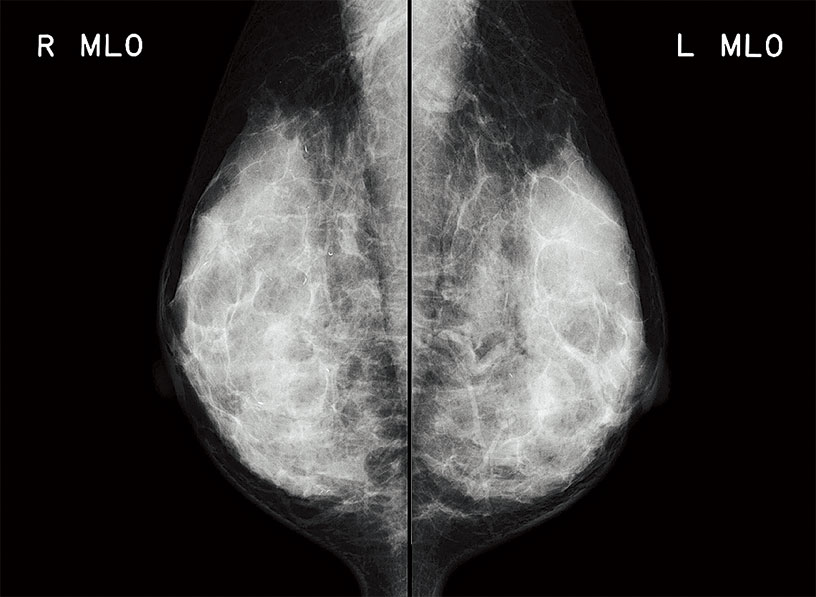

Realizing 50μm high-definition reading of mammography images

For the first time in the PRIMA series, the model is equipped with a mammography image reading function. With high definition reading and the fastest processing in the tabletop class, this model brings about a seamless workflow to your diagnosis.